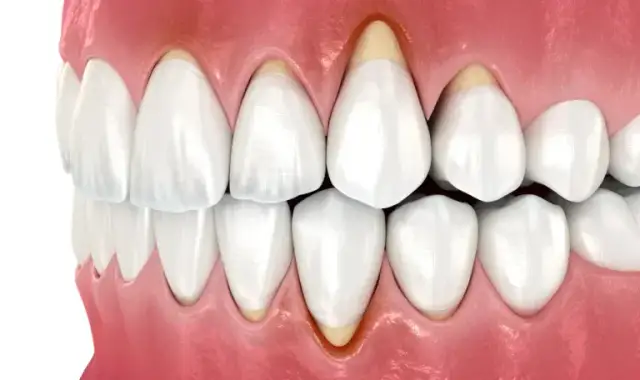

Dowiedz się, jak wygląda kamień na zębach, jakie są jego objawy oraz skutki zdrowotne. Zadbaj o zdrowie jamy ustnej i unikaj problemów!